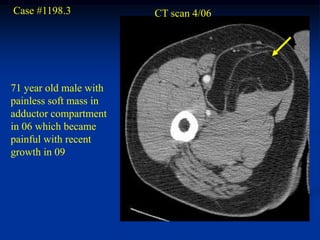

Case #1198.3 CT scan 4/06 71 year old male with painless soft mass in adductor compartment in 06 which became painful with recent growth in 09

Axial T-1 upper T-2 upper T-2 lower Cor STIR